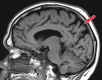

Neurodegenerative diseases are a devastating group of disorders that can be difficult to accurately diagnose. Although these disorders are difficult to manage owing to relatively limited treatment options, an early and correct diagnosis can help with managing symptoms and coping with the later stages of these disease processes. Both anatomic structural imaging and physiologic molecular imaging have evolved to a state in which these neurodegenerative processes can be identified relatively early with high accuracy. To determine the underlying disease, the radiologist should understand the different distributions and pathophysiologic processes involved. High-spatial-resolution MRI allows detection of subtle morphologic changes, as well as potential complications and alternate diagnoses, while molecular imaging allows visualization of altered function or abnormal increased or decreased concentration of disease-specific markers. These methodologies are complementary. Appropriate workup and interpretation of diagnostic studies require an integrated, multimodality, multidisciplinary approach. This article reviews the protocols and findings at MRI and nuclear medicine imaging, including with the use of flurodeoxyglucose, amyloid tracers, and dopaminergic transporter imaging (ioflupane). The pathophysiology of some of the major neurodegenerative processes and their clinical presentations are also reviewed; this information is critical to understand how these imaging modalities work, and it aids in the integration of clinical data to help synthesize a final diagnosis. Radiologists and nuclear medicine physicians aiming to include the evaluation of neurodegenerative diseases in their practice should be aware of and familiar with the multiple imaging modalities available and how using these modalities is essential in the multidisciplinary management of patients with neurodegenerative diseases.©RSNA, 2020.